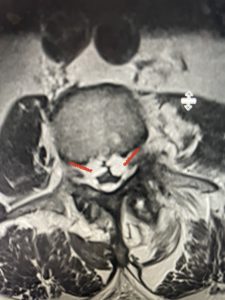

Patients with lumbar stenosis most commonly have pain, numbness, and heaviness of their legs that gets worse when they walk or stand and improves with sitting or flexing forward. Most importantly does their MRI correlate with their symptoms and/or exam? If they have L4-5 stenosis, do they have weakness of their dorsiflexion? At the level of stenosis, is the stenosis eccentric and if so, does that side correlate with the side of their symptoms? However, even on axial MRI images if one side is more affected, although both sides are to some degree, the symptomatic side does not need to be on the worst side of stenosis. This is because a bony compression on one side can compress the opposite side against the bony ring.

This 57 year-old male had a long history of low back pain and left lower extremity pain and numbness. The patient had failed conservative treatment of physical therapy and epidurals. MRI revealed tight left L2-3 and L3-4 lateral recess stenosis as well as significant right L4-5 facet arthropathy and right lateral recess stenosis as well as a grade 1 L4-5 spondylolisthesis

(Fig 2) Sagittal T2-weighted lumbar MRI demonstrating (arrow) tight lateral recess stenosis

It was felt that the patient should undergo surgical decompression and fusion at L4-5 given his spondylolisthesis. Post operatively he had an uneventful course and he had relief of his leg pain.